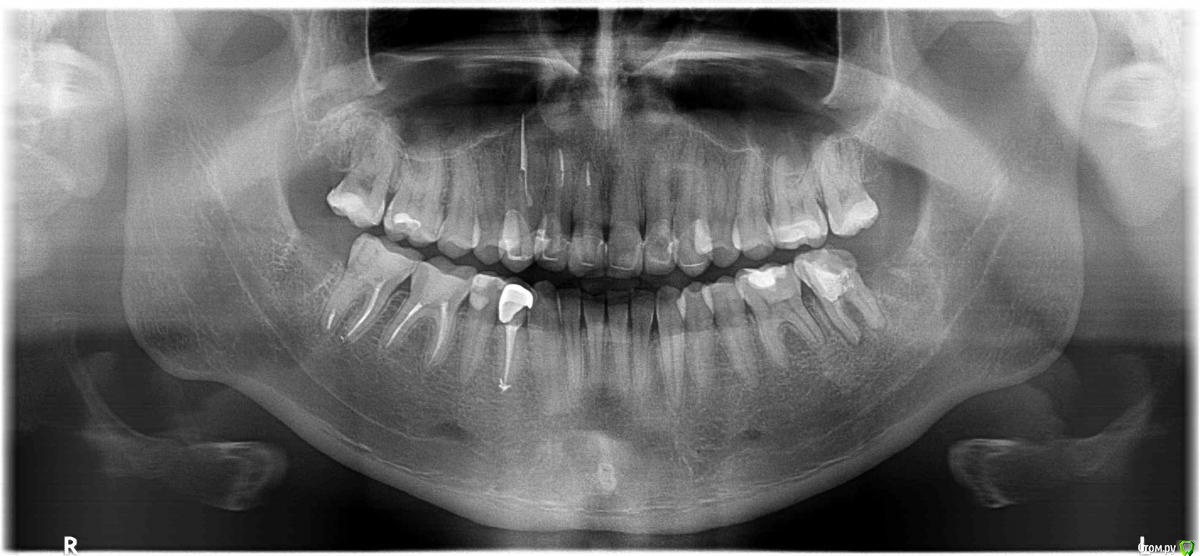

Здравствуйте,полторы недели назад была поставлена металлокерамическая коронка на правую нижнюю четверку,позавчера при чистке щеткой почувствовал слабую боль,боль как оказалось происходит если надавить коронку в сторону дальних зубов.

Стоматолог сказала что возможна причина в  десне(сказала что десна у меня рыхлые) предложила полоскать рот хлоргексидином,газированной минеральной водой и пить аскорутин и если улучшений не будет,то причина в соседней пятерки и придется ее депульпировать.